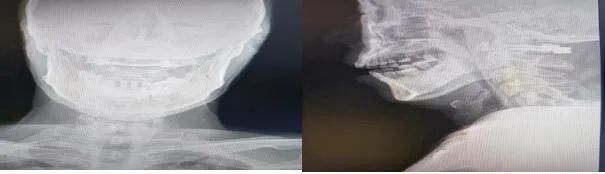

患者男性,50岁,高处坠落致寰椎前后弓骨折并四肢不全瘫,随后到市中心医院就诊,医生在对其进行详细检查后,决定为其实施寰椎骨折切开复位椎弓根钉棒固定术。由于上颈椎解剖结构的特点,手术的风险性较大,特别是需要内固定的手术。加之上颈部疾患常常伴有解剖结构的变异,更增加了上颈椎手术的风险性与难度,开展此类手术必须要经验丰富,技术过硬的医师。

骨一科医生对患者经过全面的术前检查后,严密制定手术方案。由程福宏主任主刀,葛大明副主任医师配合,顺利完成了寰椎骨折切开复位椎弓根钉棒固定术,手术最大可能的减少了固定节段,最大程度的保留了颈椎的活动度,术后患者四肢肌力较术前明显恢复。目前患者已顺利出院,生活可自理。